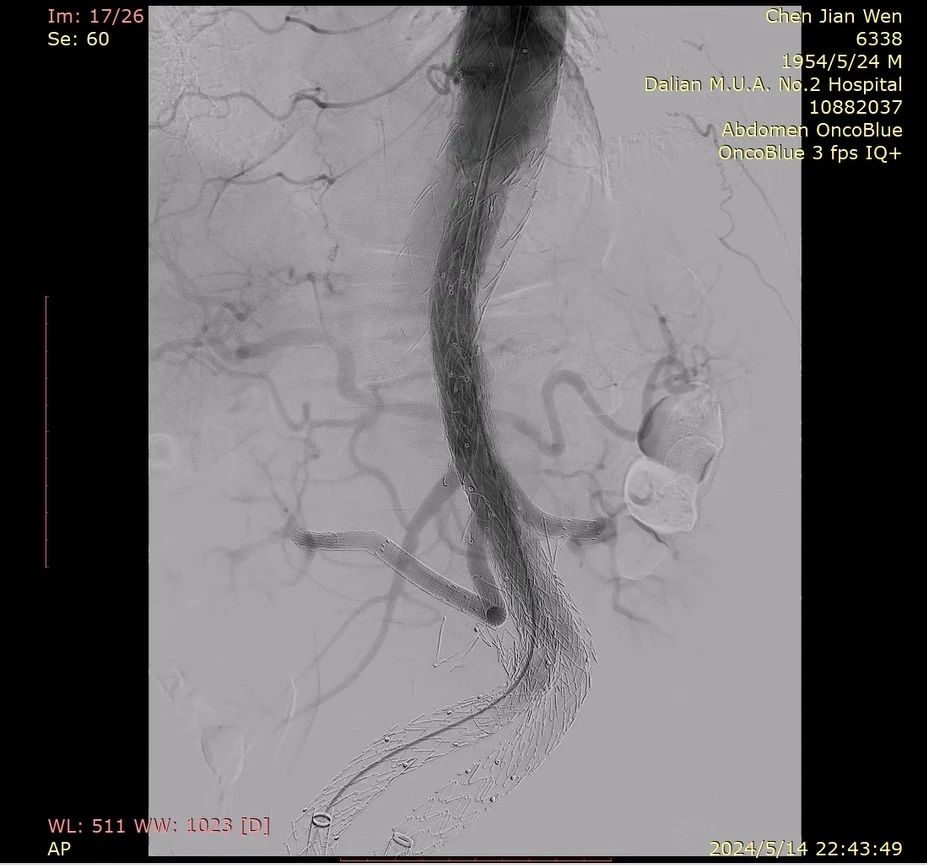

李磊教授详细介绍了一例IBD支架四分支重建复杂腹主动脉瘤病例。患者男性,69岁,既往行TEVAR及EVAR,诊断为主动脉内脏四分支区巨大动脉瘤(直径76.5mm),原腹主覆膜支架裸支架脱落,胸主动脉扭曲,髂动脉扭曲。李磊教授拟定的手术策略为:以原胸主支架起始端为腹主支架近端锚定区,腹主支架两侧分支接IBD支架,两个IBD支架分别重建双肾动脉、腹腔干和肠系膜上动脉,超选分支放入小覆膜支架与IBD支架远端桥接。

改造双侧IBD支架,在分支对侧上方开口并缝合VB支架

器械选用腹主动脉支架32*16*145,G-iliac 1612*80*150,G-iliac 1612*60*130,VB 7*50,VB 8*50,VB 10*100,SilverFlow PS-C-10080XL,SilverFlow PS-C-12060XL。

术中肾动脉走行扭曲且狭窄,超选困难,在Fustar可调弯鞘的辅助下,完成超选。IBD显影点清晰便于对位,支架柔顺性较好,节省了手术时间。

术后造影,内脏四分支血流通畅,无内漏。